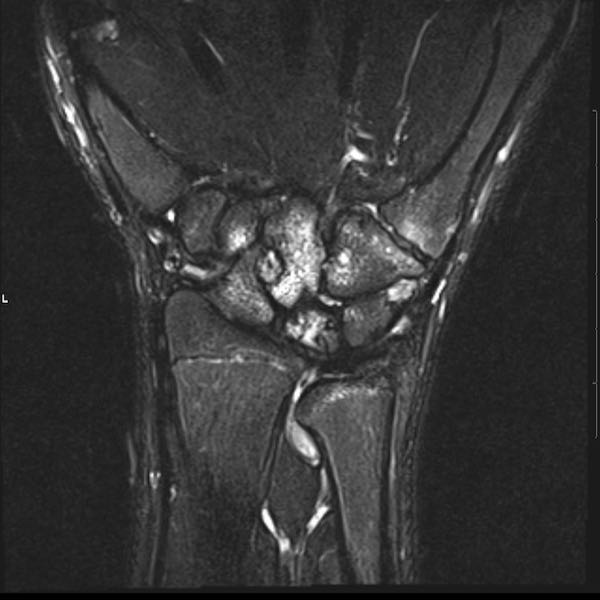

Tiếp tục xem hình ảnh MRI của bệnh nhân này.

Hình ảnh MRI:

Tràn dịch lan tỏa tất cả các khớp cổ tay.

Phù tủy xương lan tỏa tất cả các xương cổ tay.

Bào mòn xương, ví dụ tại xương thuyền, xương đầu và xương móc.

Phá hủy khe khớp và sụn khớp, rõ nhất tại khớp STT và CMC4/5.